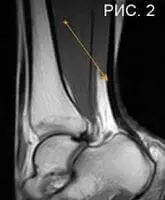

На представленных рисунках: схематическое изображение голени (Рис 1), и изображение ахиллова сухожилия в норме при магнитно-резонансной томографии голеностопного сустава (Рис 2), указано стрелкой.